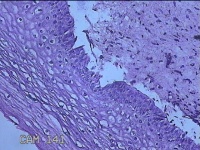

性别

女

年龄

34岁

临床诊断

宫颈上皮内肿瘤?

一般病史

月经干净7天,宫颈HPv18,12亚型阳性。

标本名称

大体所见

灰白粉红色组织0.5x0.3x0.2cm一块。

图1